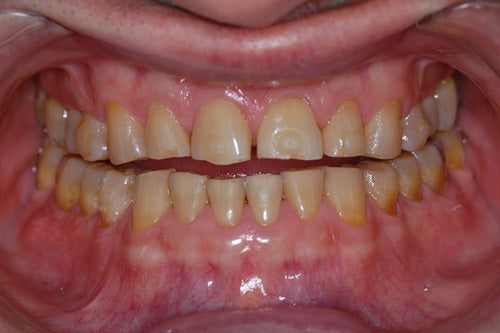

Composite repair for uneven incisal wear

Posted on October 19 2022

Introduction: Patient did not like the unevenness of his front teeth. Upon close examination, I observed both #'s 8 & 9 have a palatal inclination. I can now add composite... Read More